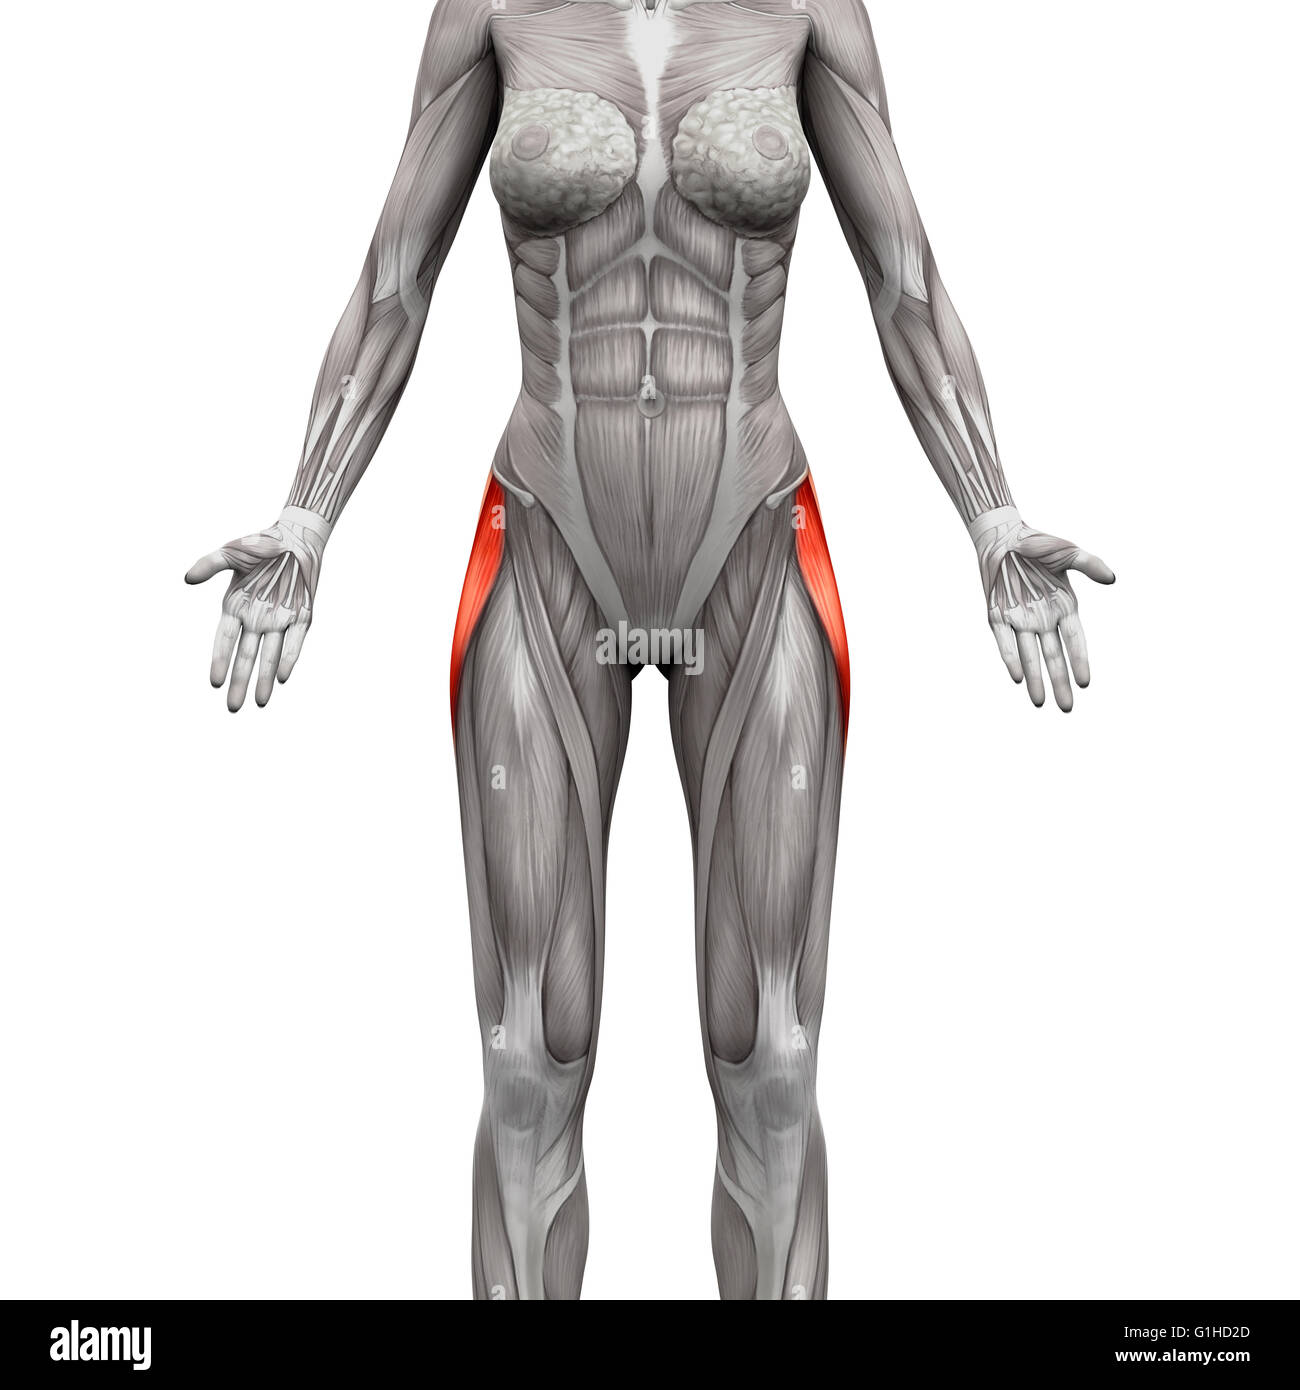

Tensor Fasciae Latae Muscle - Anatomy Muscles isolated on white - 3D illustration Stock Photohttps://www.alamy.com/image-license-details/?v=1https://www.alamy.com/stock-photo-tensor-fasciae-latae-muscle-anatomy-muscles-isolated-on-white-3d-illustration-104260309.html

Tensor Fasciae Latae Muscle - Anatomy Muscles isolated on white - 3D illustration Stock Photohttps://www.alamy.com/image-license-details/?v=1https://www.alamy.com/stock-photo-tensor-fasciae-latae-muscle-anatomy-muscles-isolated-on-white-3d-illustration-104260309.htmlRFG1HD2D–Tensor Fasciae Latae Muscle - Anatomy Muscles isolated on white - 3D illustration